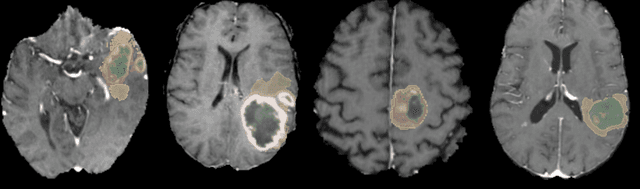

Abstract:Brain tumor segmentation is a critical task for patient's disease management. To this end, we trained multiple U-net like neural networks, mainly with deep supervision and stochastic weight averaging, on the Multimodal Brain Tumor Segmentation Challenge (BraTS) 2020 training dataset, in a cross-validated fashion. Final brain tumor segmentations were produced by first averaging independently two sets of models, and then custom merging the labelmaps to account for individual performance of each set. Our performance on the online validation dataset with test time augmentation were as follows: Dice of 0.81, 0.91 and 0.85; Hausdorff (95%) of 20.6, 4,3, 5.7 mm for the enhancing tumor, whole tumor and tumor core, respectively. Similarly, our ensemble achieved a Dice of 0.79, 0.89 and 0.84, as well as Hausdorff (95%) of 20.4, 6.7 and 19.5mm on the final test dataset. More complicated training schemes and neural network architectures were investigated, without significant performance gain, at the cost of greatly increased training time. While relatively straightforward, our approach yielded good and balanced performance for each tumor subregions. Our solution is open sourced at https://github.com/lescientifik/xxxxx.